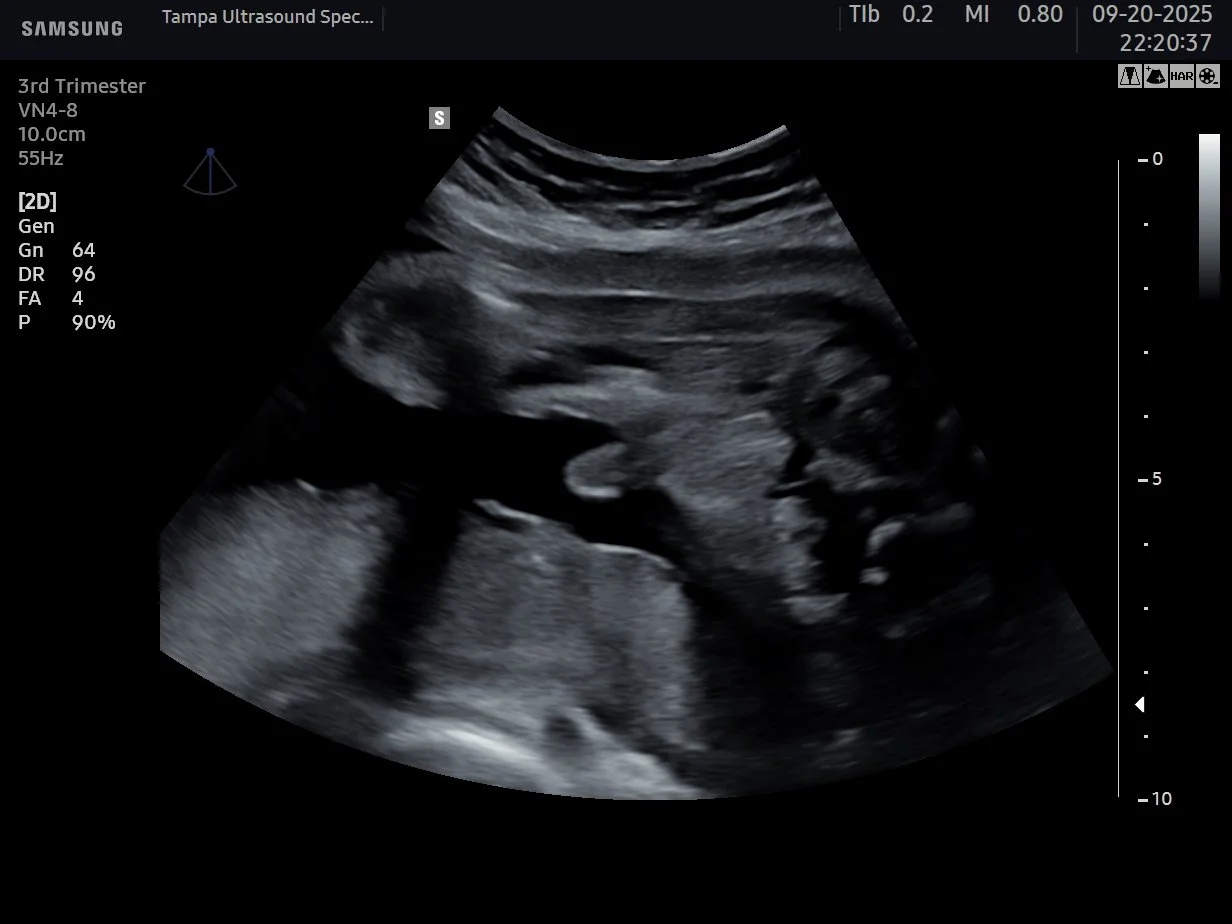

Week 34 and beyond

Call us first

Still possible at any stage. Call or text us and we will find the best option for where you are in your pregnancy.

3D/4D Baby Ultrasound Tampa, FL -- HD Live Sessions (Best Weeks 23 to 33)

See your baby's face, hands, and real-time movements in breathtaking 3D/4D/5D/HD detail on our large projection screen with LED ceiling. Available at any stage of pregnancy -- best results between weeks 23 and 33. The sweet spot is weeks 26 to 30 when baby has developed facial features and still has plenty of space to move. No referral needed. Se habla espanol. From $139.

See your baby's face, hands, and real-time movements in breathtaking 3D/4D/5D/HD detail on our large 65" screen with LED ceiling. Available at any stage of pregnancy — best results between weeks 23 and 33. The sweet spot is weeks 26 to 30. No referral needed. Se habla español. From $139.

When is the best time to get a 3D/4D ultrasound in Tampa? 3D/4D ultrasound is available at any stage of pregnancy at Tampa Ultrasound Specialist. For the best images we recommend weeks 23 to 33, with the sweet spot being weeks 26 to 30 when baby has developed facial features and still has plenty of room to move.